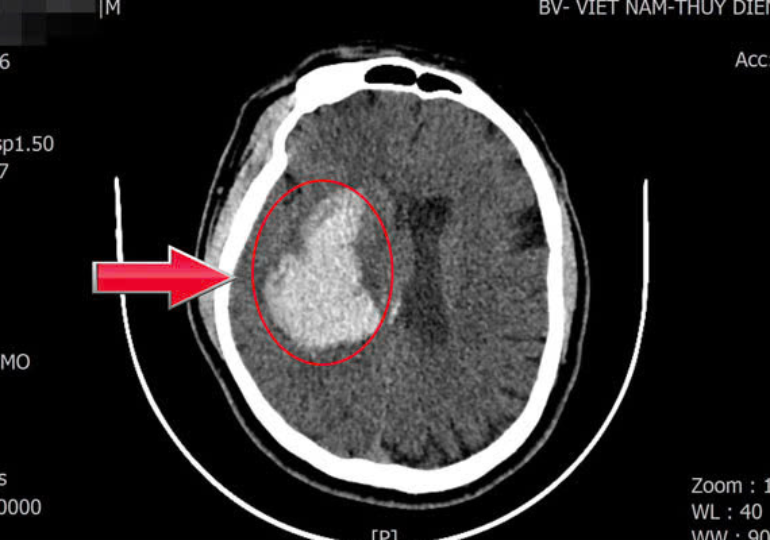

Ngay sau khi tiếp nhận, các bác sĩ đã tiến hành chụp CT sọ não cấp cứu. Kết quả cho thấy bệnh nhân bị xuất huyết não kèm tụ máu trong nhu mô não, gây chèn ép các tổ chức não xung quanh. Trước diễn biến nặng và nguy cơ đe dọa tính mạng của người bệnh, ê-kíp đã nhanh chóng hội chẩn và quyết định phẫu thuật cấp cứu lấy khối máu tụ.

Hình ảnh chụp phim não của bệnh nhân. Ảnh: BVCC.